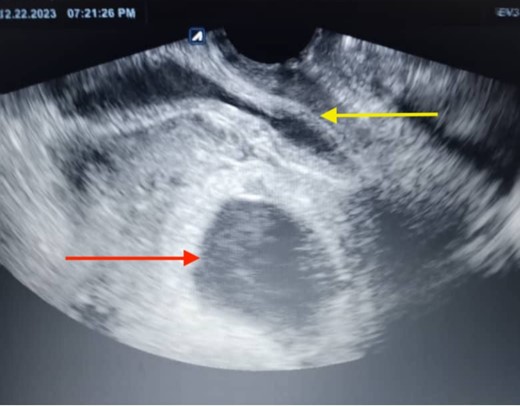

Furthermore, hemoglobin levels dropped to 9.7 g/L the following day and further deteriorated to 8.7 g/dl as the patient’s hemodynamic condition worsened, with her pulse accelerating to 120 beats per minute. Ultrasound revealed a moderate amount of free fluid in the pouch of Douglas and Morrison’s Pouch with an eventration in the previous cesarean scar and the gestational sac descending to the level of this scar and starting to form an occlusal line at the upper part of the uterus (Fig. 1).

The ultrasonographic imaging conducted the day following the patient’s hospital admission revealed a ruptured gestational sac (the lower arrow), which was apparent outside the uterus. The uterine mass was visible on one side (the upper arrow), and the gestational mass was on the other side.